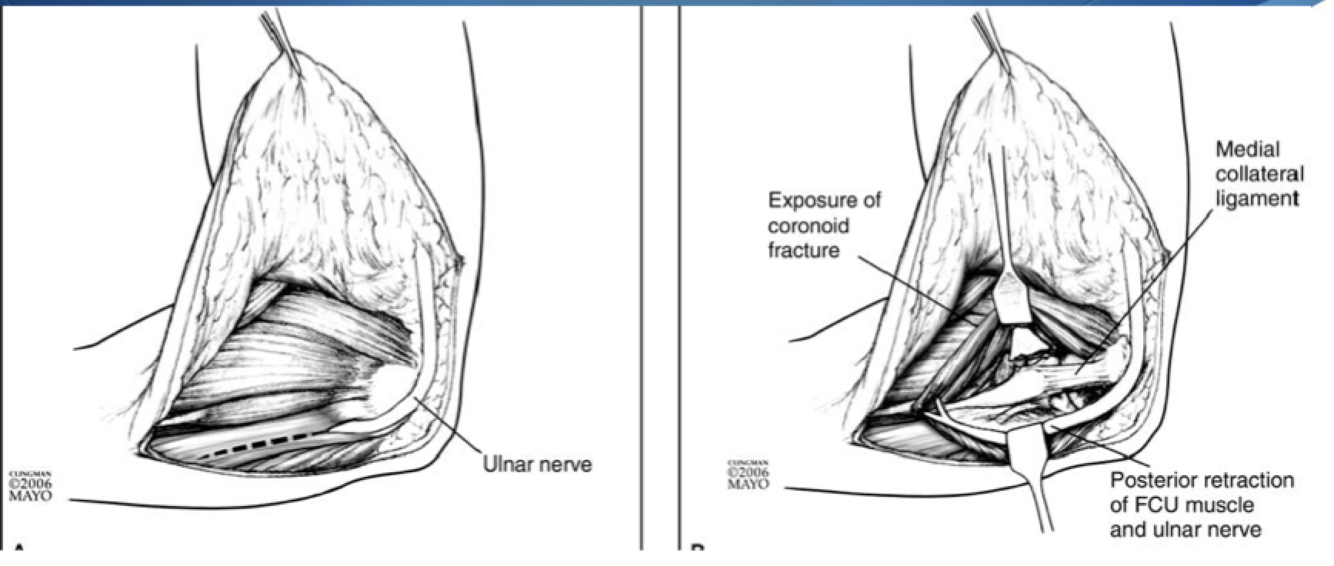

FCU Split

Interval: None, between two heads of FCU (Ulnar N.)

Approach: Identify, unroof and protect median n. Split two heads of FCU and elevate anteriorly. Care to be taken not to injure MUCL

Dangers: MUCL, Ulnar N. Median N. Brachial A.

Modified Taylor and Scham

Interval: ECU (PIN), FCU (Ulnar N.)

Approach: Dissect down to subcutaneous boarder of ulan and lift everything anteriorly. Akin to the boyd but on the medial side. Gives access to base of coranoid/sublime tubercle

Dangers: Ulnar N., MUCL